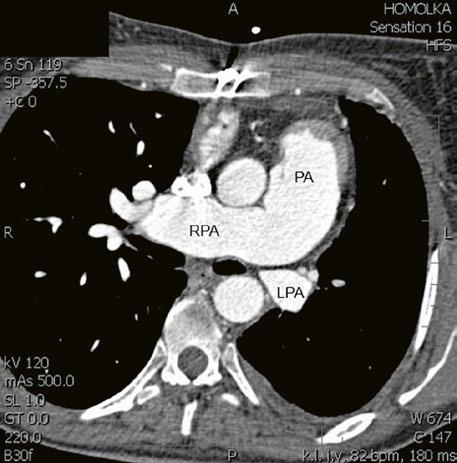

Supravalvární pulmonální stenóza a stenózy větví plicnice bývají součástí komplexních VSV (např. Fallotovy tetralogie) nebo syndromů (Williamsův syndrom, syndrom Noonanové, syndrom vrozené rubeoly, Alagillův syndrom aj.) (Obr. 45.39). Získané stenózy větví plicnice, ale i úplný uzávěr větve plicnice můžeme vidět po spojkových operacích podle BlalockaTaussigové (Obr. 45.40, Obr. 45.41). Pro zobrazení supravalvárních a periferních stenóz plicnice je optimální CT angiografie (Obr. 45.40, Obr. 45.41, Obr. 45.42, Obr. 45.43).

Obr. 45.40 CT angiografie, 8mm stenóza a deformace levé větve plicnice (šipka) po spojkové operaci podle BlalockaTaussigové v dětství LPA – levá větev plicnice, PA – kmen plicnice, RPA – pravá větev plicnice

Obr. 45.42 CT angiografie. Dilatace kmene plicnice (PA), periferní stenóza v oblasti bifurkace a odstupu pravé větve plicnice (RPA) označena šipkou, odstup levé větve plicnice (LPA) je také lehce zúžen.

Obr. 45.41 Uzávěr levé větve plicnice jako následek provedené spojky podle BlalockaTaussigové v dětství, CT angiografie

Obr. 45.43 CT angiografie, šipkou označena významná odstupová stenóza levé větve plicnice (LPA), lehčí stenóza odstupu pravé větve plicnice (RPA), kalcifikace v oblasti pulmonální chlopně

AO – aorta

Pro zobrazení plicnice a jejích větví je nejvhodnější CT angiografie (Obr. 45.40, Obr. 45.41, Obr. 45.42, Obr. 45.43). Magnetická rezonance zhodnotí velikost a funkci pravé komory i regurgitační frakci u pulmonální regurgitace (Video 45.41).